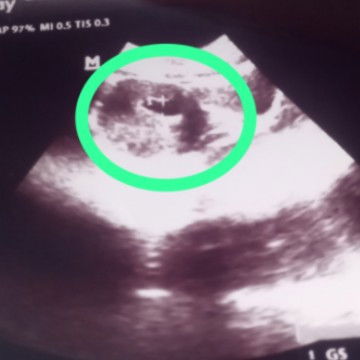

Tolong bantu jelasin ya Bun.. apa ini Dede bayi nya ?? Kehamilan 10 Minggu

Coba dilihat di print USG sebelah kanan bawah bun. Kalau ada GS berarti itu kantong kehamilan, kalau sudah ada CRL berarti itu sudah ada janin nya

coba ka itu liat di hasil usg nya ada GS (ukuran kantong kehamilan) ada CRL (ukuran janin) ada EDD (perkiraan tgl lahir)

Iya bun itu kantong kehamilannya. Nanti kalo usg jangan lupa tanyain ke dokternya langsung karena memang ahlinya